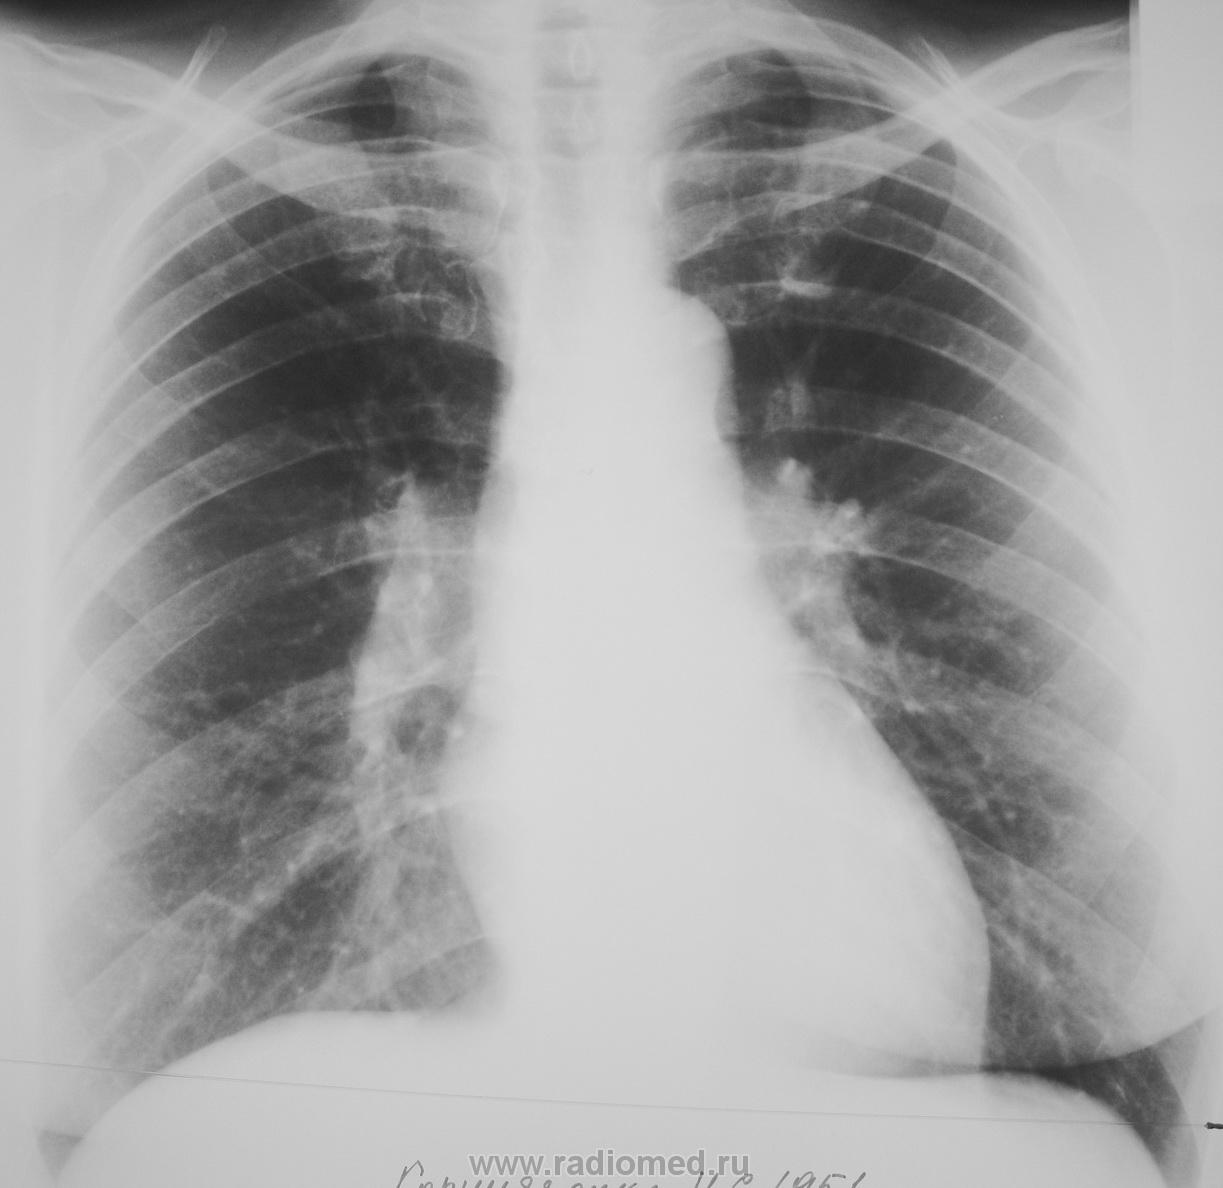

Извините коллеги забыл откопировать обычную сегодняшнюю обзорную прямую..- томограммы от 14.04.2011 вашему вниманию. Обзорка за июнь прошлого года . В анаменезе в 2010 июль опрерирована Sa в фиброзном узле матки.

заполненную ретенционную бронхиальную кисту легкого

Ретенционные кисты должны иметь "свою историю", они за год не растут...тут годы и годы нужны. В первую очередь исключайте метастатическое поражение.

+1.Возможно,она имела историю и в данном случае: зачастую на Rg виден только фиброз.к-ый можно пропустить,а уж Tg приоткрывает слои))) Типичная заполненная ретенционная киста